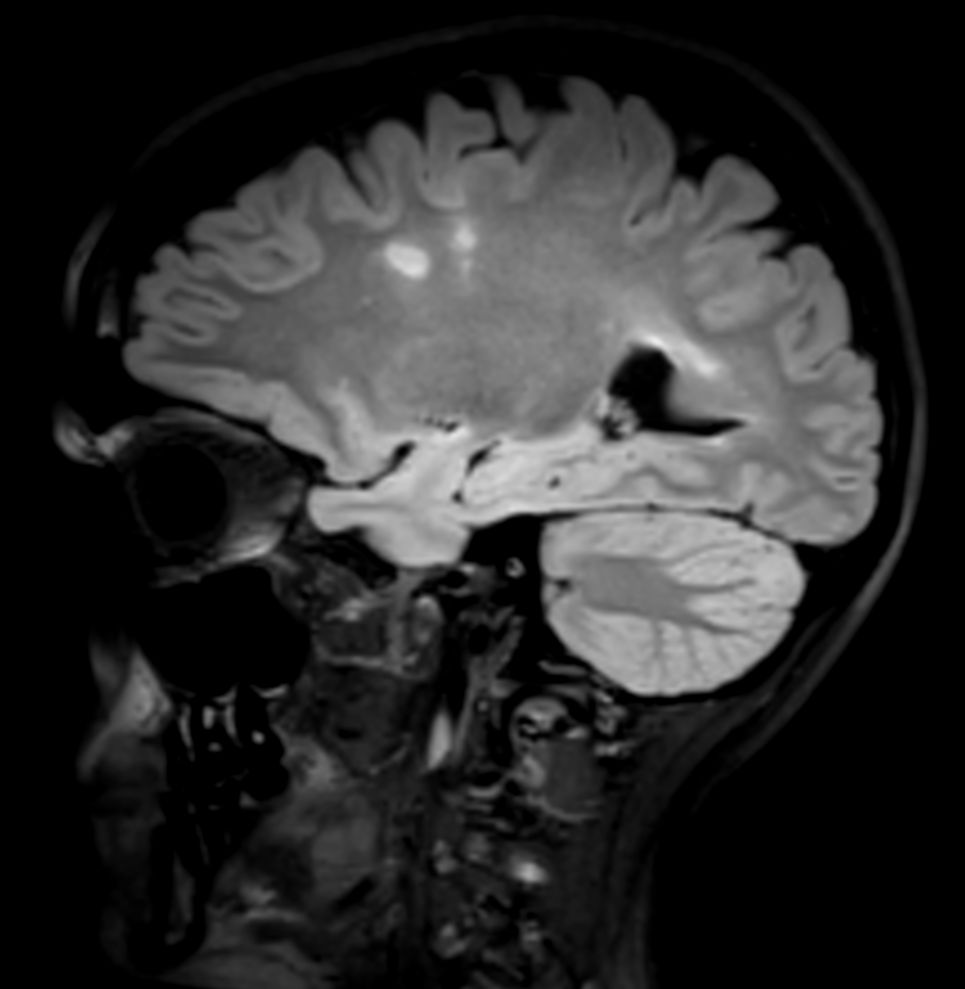

SWI sequence has a high sensitivity to enhance contrast for deoxygenated (venous) blood or calcium deposits. This may help, when used in combination with other clinical information, in the diagnosis of various neurological pathologies. 3D imaging lets you acquire high resolution data in multiple directions in one scan. Isotropic voxel size enables reformats in any plane without loss of resolution. FLAIR* requires offline post processing combining the contrast of 3D FLAIR and 3D SWI EPI into a single image. This enables the visualization of Central Vein Sign, mapping subcortical veins onto 3D FLAIR contrast images.